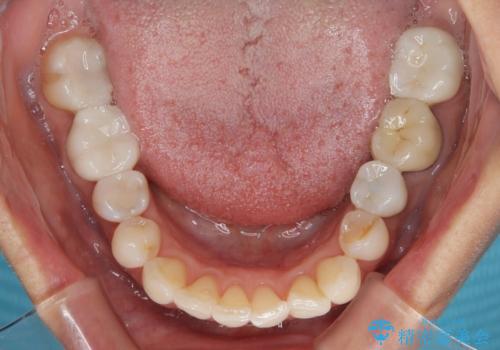

- 目立つ銀歯やむし歯、前歯のデコボコを気にして来院された患者様です。

デコボコはある程度改善できれば良いとのことでしたので、インビザラインの廉価版を用いて矯正治療を行うこととしました。

むし歯治療は、症状のある歯を矯正治療前に処置し、概ね歯列が整ったところで残りのは全て処置し、最後にインビザラインで歯列を仕上げることで、無駄なく治療を進めて行くこととしました。

しっかりと装着時間を守ってくださり、来院のタイミングに合わせてインビザラインの装着期間を調整するなど、協力いただいたおかけで、1年半の期間で全てを終えることができました。